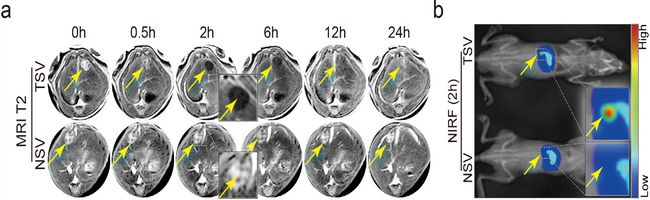

附属第一医院匡铭、帅心涛教授交叉学科团队在医用纳米探针方面取得新进展